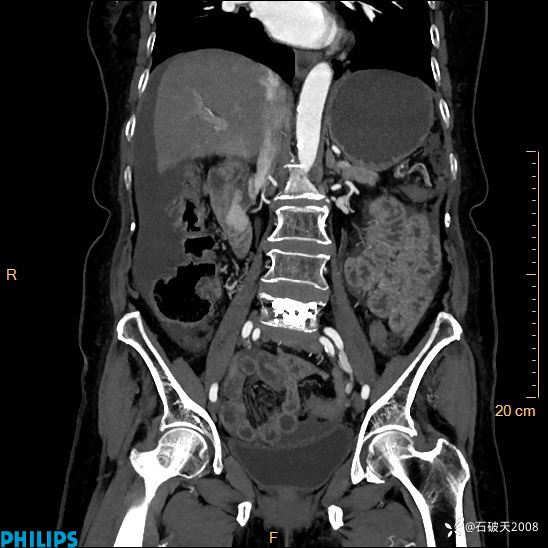

半年前住院没发现问题,近期腹痛来诊

女82岁 主 诉:腹痛半月,加重3天

MIP